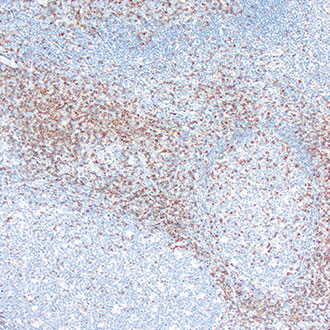

CD45

CD45 -